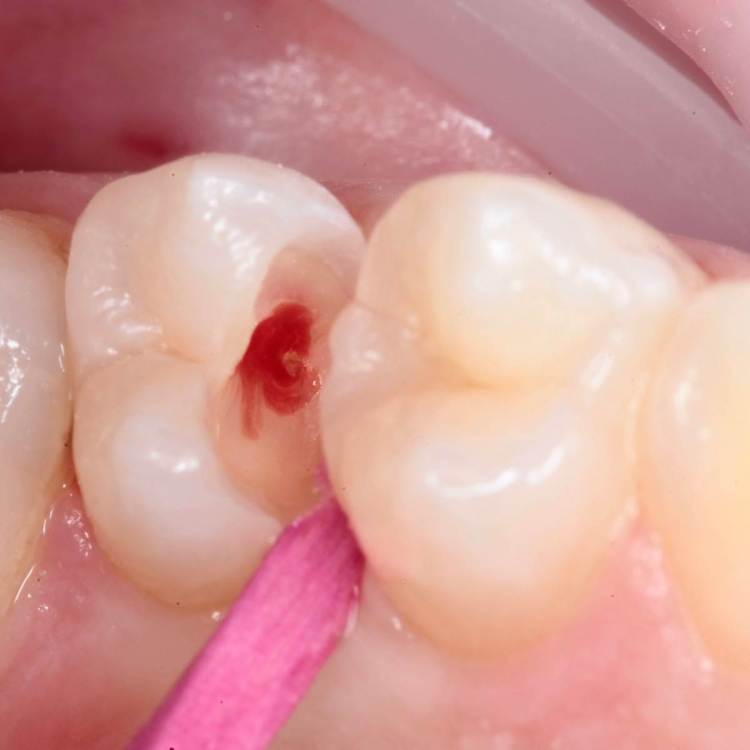

Как часто мы сталкиваемся с такими процессами и как редко пациент сам предъявляет какие то жалобы на такие зубы. Максимум это… застревание пищи.

Глубина полости ниже уровня десневого края на 2-3 мм. Коагуляция, ENDO, анатомичный билдап, проверка качества реставрации и отсутсвие нависающего края (интерпроксимальный снимок), рекомендации.